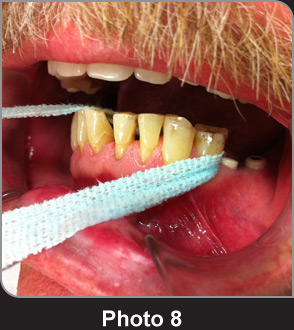

寬牙線X-Ribbon?用于清潔寬牙縫,柔嫩和粗紗材質清潔牙縫很得心應手。

如果牙縫的間隙空間允許,寬牙線X-Ribbon?可以聯(lián)合一根毛牙線,穿過齒橋間隙清潔牙縫,效果奇佳。